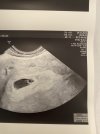

Jestem po wizycie .

Widoczny jest pęcherzyk ciążowy z pęcherzykiem żółtkowym .

Niby wszystko ok na tym etapie ale czuję jakiś niedosyt 😒 liczyłam że zobaczę coś więcej 😞

No nic w środę mam kolejną wizytę tym razem już u swojej gin 🥳